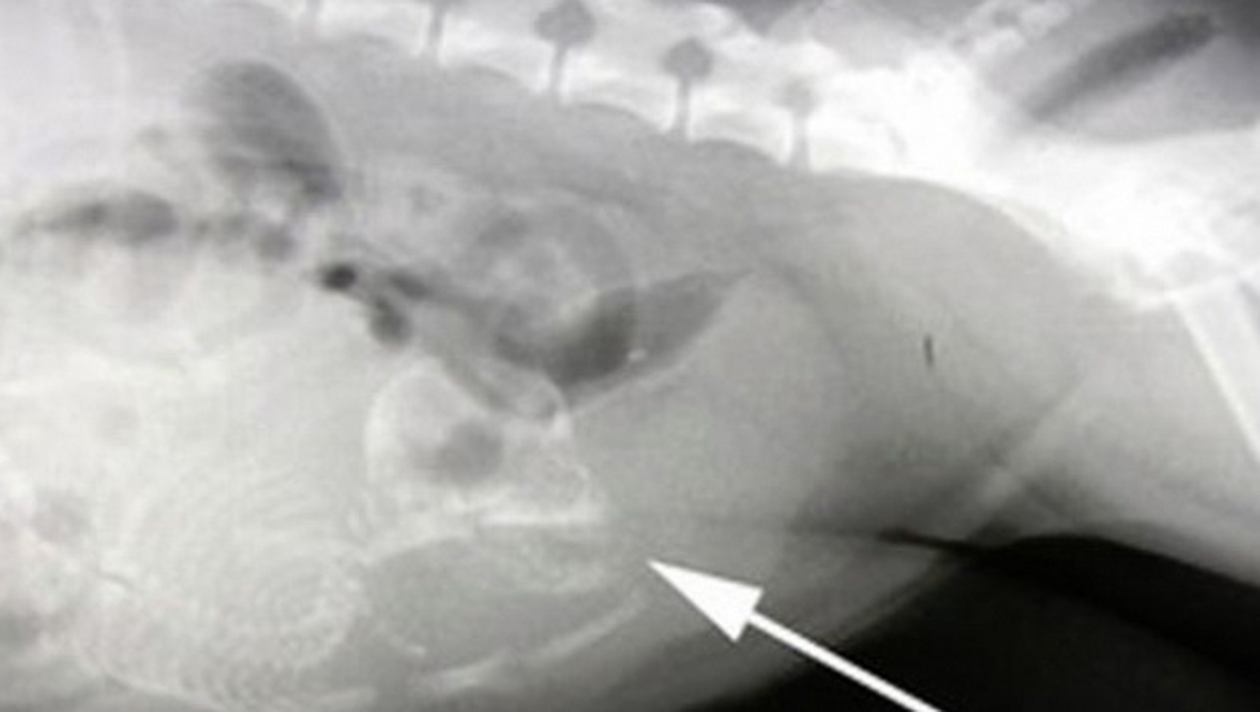

Un baietel de 2 ani din China a ajuns de urgenta la spital, pentru ca stomacul il durea si I se umflase foarte tare. Medicii i-au facut o ecografie si au fost socati cand s-au uitat pe imagini.

Medicii au vazut pe ecografie ca baiatul avea in corp fetusul nedezvoltat al unui frate geaman. Xiao a fost operat imediat si acum va duce o viata normala.

Baiatul ar fi trebuit sa aiba un farte geaman identic, dar acesta nu s-a mai dezvoltat si a fost pur si simplu „absorbit” in abdomenul lui Xiao.

Daca operatia nu ar fiu fost facuta la timp, baietelul ar fi murit. Fetusul avea aproximativ 25 de cm lungime.